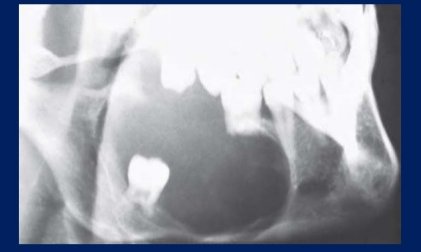

- Dentigerous cysts have the potential, to attain a large size, often it is the pronounced facial asymmetry .

Radiographic features :

- generally reveals a unilocular radiolucency associated with crowns of unerupted teeth ( multilocular effect can be seen, in large cysts due to bony trabeculations).

- Cysts have a well defined sclerotic margin, unless when they are infected then the margins are poorly defined.As compared to the other jaw cysts,